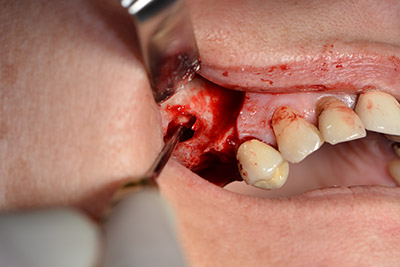

The implant was then placed and the bone built up. In this case, because of the size of the augmentation region, autologous bone chips, harvested with an osseous trap as drilling chips from implantation 16 and fenestration 14, were mixed with bone replacement material.

An absorbable membrane was used as the barrier in the buccal direction and covered the augmentation. Finally, saliva-proof sutures were placed (Fig. 15 to 19).